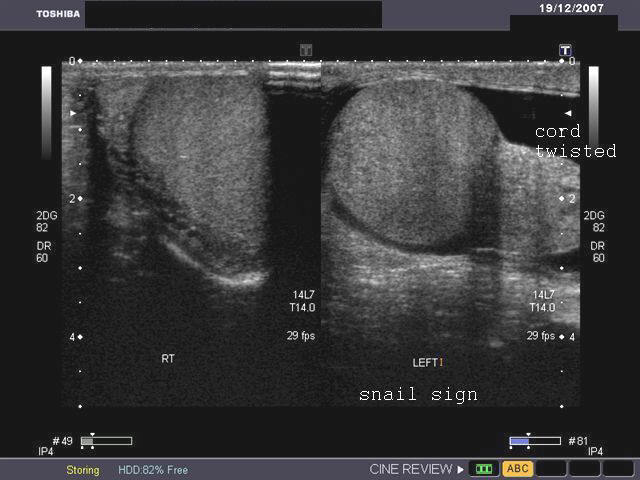

Torsion of testes

Ultrasound images showing torsed left testes. Testicular torsion occurs most commonly due to long spermatic cord. There are 2 types of torsion: extravaginal (usually in newborns) and intravaginal torsion (usually at puberty). In the ultrasound images above, the left testes appears swollen and mildly hypoechoic. A small left hydrocele is also present. On color doppler imaging, the left testes shows absence of blood flow. The "snail sign" is also seen in the left testes, caused by swollen testes (shell of snail) and twisted, bulky spermatic cord (body and head of snail). These ultrasound images suggest torsion of the left testes. The affected testes was removed and found to be gangrenous. Images taken using a Toshiba Xario color doppler and ultrasound machine, courtesy of Dr. Gunjan Puri, Surat, India.